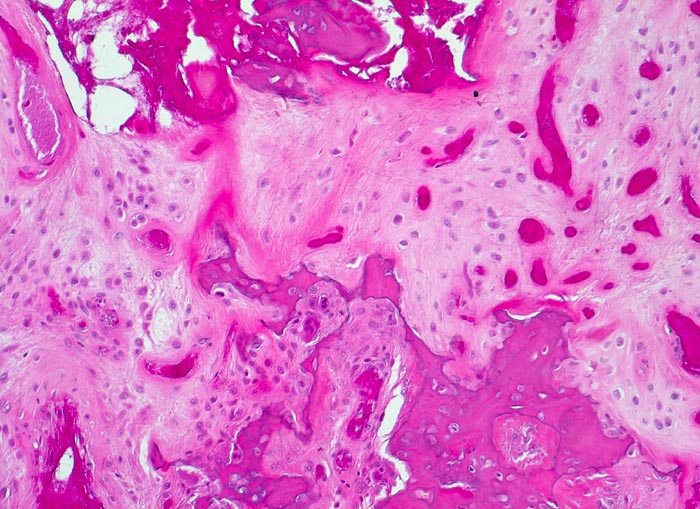

aseptische Femurkopfnekrose

Knochen, Femurkopf

Nekrosezone: kleine avitale Knochenfragmente liegen eingebettet in neugebildete fasrige extrazelluläre Matrix. Der ortsständige Knochen wird von Osteoklasten abgeräumt.

Der Patient ist Gastwirt von Beruf und klagt über rasch zunehmende Schmerzen im rechten Hüftgelenk, die auch nachts auftreten. Aufgrund der invalidisierenden Schmerzen wird eine Endoprothese eingesetzt.